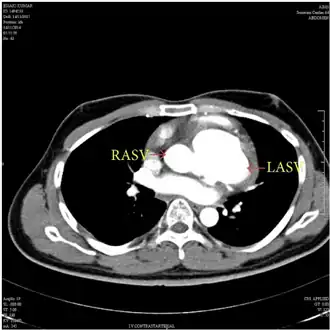

Diagnostic methodEchocardiogram, cardiac CT scan, cardiac MRI scan

The first step in diagnosis is typically transthoracic echocardiography. However, if surgery is planned or if the standard echocardiogram lacks sufficient detail, then one or more additional studies are recommended. These studies include transesophageal echocardiography, 3D echocardiography, CT Angiography and aortic angiography.[4] Cardiac MRI may be another option.[2]